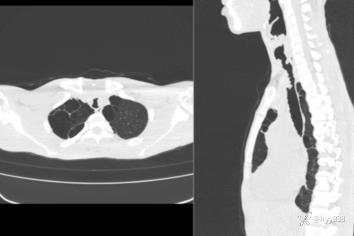

性别:男

年龄:38岁

简要病史:慢性声音嘶哑,最近体重减轻。

实验室检查:白细胞稍高,HPV阳性

体查:吸气喘鸣

胸部CT平扫